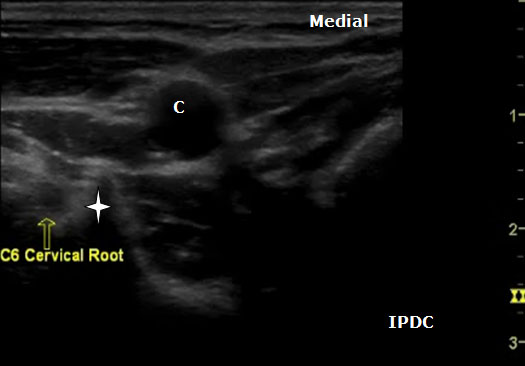

The sonoanatomy of the anterior and posterior tubercles associated with the transverse processes of the C4, C5, C6, and C7 vertebrae are used to identify their respective cervical nerve roots. The C7 vertebral body demonstrates an absent or rudimentary anterior tubercle with a prominent posterior tubercle (Figure 7). The anterior and posterior tubercles are seen as hyperechoic outlines with associated acoustic shadowing (hypoechoic area below). C6 has a sharp and prominent anterior tubercle and a shorter posterior tubercle. The nerve roots are viewed as homogeneous oval hypoechoic structures that exit through the transverse processes of the corresponding vertebral level. For example, the C6 nerve root will be seen between the anterior and posterior tubercles of the transverse process of C6 (Figures 8 & 9). The nerve roots differ in appearance from peripheral nerves below the clavicle which have a more hyperechoic appearance. As the transducer progresses to the more cephalad nerve roots, the anterior and posterior tubercles assume similar size characteristics (Figure 10) that have been referred to as the “2 humped camel sign.”[17] In approximately 90% of cases at the C7 level (Figure 7), the vertebral artery can be visualized prior to its entrance into the foramen at the C6 level.[10][18] Other important structures to visualize in the neck to assist with orientation include the thyroid, internal carotid artery, and jugular vein.

Figure 8. An axial ultrasound image at the C6 vertebral level demonstrating the nerve root (arrow) between the prominent anterior tubercle (star) and smaller posterior tubercle. LC= Longus Colli Muscle. C = Carotid Artery.

Figure 9. An axial ultrasound image at the C6 vertebral level demonstrating the nerve root and the prominent anterior tubercle (star). C = Carotid Artery.

Ultrasound Technique for Cervical Nerve Root Block

The spinal nerve roots are identified on the basis of different morphologies of the transverse processes of each vertebral body. The patient is positioned in either the lateral decubitus position with visualized side up or in the supine position. In the supine position the cricoid cartilage should be palpated as a C6 landmark. Position a high-frequency linear array ultrasound transducer (5 to 12 MHz) lateral to this location. The transducer is applied transversely to the lateral aspect of the neck, and a short axis view is obtained. The carotid artery, internal jugular, vein, and thyroid should be identified. In the supine position the transducer is situated and moved laterally in the axial direction until the transverse processes are identified. The transverse processes are lateral to the carotid artery.

The level of the cervical spine is identified by the corresponding morphology of the transverse processes. At the C6 level the prominent anterior tubercle will be visualized with the longus colli muscle medially. The ultrasound transducer should be moved in a craniocaudal direction to further confirm the appropriate cervical level. The C7 level will have a prominent posterior tubercle, and the vertebral artery will be visualized medially in a majority of cases. As the transducer is moved cephalad from the C6 level, the anterior and posterior tubercles will assume a similar shape with the nerve root lying in between. In cases in which the identification of the cervical level is challenging, other sonoanatomy clues can be utilized.

If the patient is positioned in the lateral position, the transducer can be rotated in a vertical position near the posterior aspect of the neck to obtain a longitudinal midline scan. With this view the cervical spinous processes can be counted to identify the appropriate level. C1 lacks a spinous process. Once the appropriate level is identified, the transducer is then rotated back to the transverse axial view. When the nerve root and appropriate tubercle structures have been located, the transducer can be moved lateral so that one only sees these structures and the carotid artery is out of the field of view. Doppler sonography should be utilized to identify critical vessels within the vicinity of the cervical nerve roots. Due to bony dropout artifact, one is not able to trace the cervical nerve root or injected materials (i.e. radiographic contrast) within the foramen.